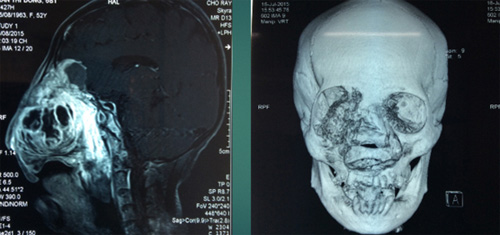

Sau khi khám, chụp cắt lớp, bác sĩ cho biết, khối u đã xâm lấn, gây mù hoàn toàn mắt phải, ăn thủng xương sàn sọ, màn cứng, tấn công vào mô não. Ngay bác sĩ tại bệnh viện Chợ Rẫy cũng kêu gọi từ phòng Công tác xã hội hỗ trợ kinh phí phẫu thuật.

Bác sĩ Nguyễn Ngọc Khang (Phó trưởng khoa Ngoại Thần kinh) cho biết, vào tháng 6/2015, bà Đông được chuyển từ bệnh viện tuyến dưới lên. Lúc đó, khối bướu lớn, diện tích 8x10 cm. Sau khi hội chẩn liên chuyên khoa gồm chẩn đoán hình ảnh, tai mũi họng, ngoại thần kinh, mắt, gây mê hồi sức…, các bác sĩ chẩn đoán bà Đông bị u dây thần kinh.

Trước nguy cơ khối u xâm lấn não sẽ gây tử vong, bác sĩ nhờ sự hỗ trợ viện phí từ Phòng Công tác xã hội. Bác sĩ khoa Tai mũi họng và Ngoại thần kinh đã phối hợp thực hiện ca mổ. Ca mổ này đối mặt rất nhiều rủi ro vì khối u đã xâm lấn đến hệ thần kinh thị giác, khứu giác… Nếu sơ hở, bệnh nhân có thể bị liệt nửa người hoặc tử vong ngay trong khi mổ.

Sau 6 tiếng “cân não”, khối u được bóc tách thành công. Sau đó, bác sĩ vá màng cứng, đặt lưới titanium lót sàn sọ để tránh nguy cơ vi khuẩn theo đường mũi tấn công lên não.

Sau ca phẫu thuật, kết quả giải phẫu bệnh phẩm, chuyên khoa nhận định, bà Đông bị u xương ác tính. Đây là căn bệnh hiếm gặp trong y văn. Vài năm, bệnh viện Chợ Rẫy mới gặp một ca bệnh này.

Ca phẫu thuật bóc tách khối u khiến toàn bộ hốc mắt, hốc mũi của bệnh nhân gần như trống rỗng. Do đó, bác sĩ yêu cầu bệnh nhân phải tuân thủ chỉ định hóa trị, xạ trị tránh trường hợp đại mô thịt qua hốc mắt.